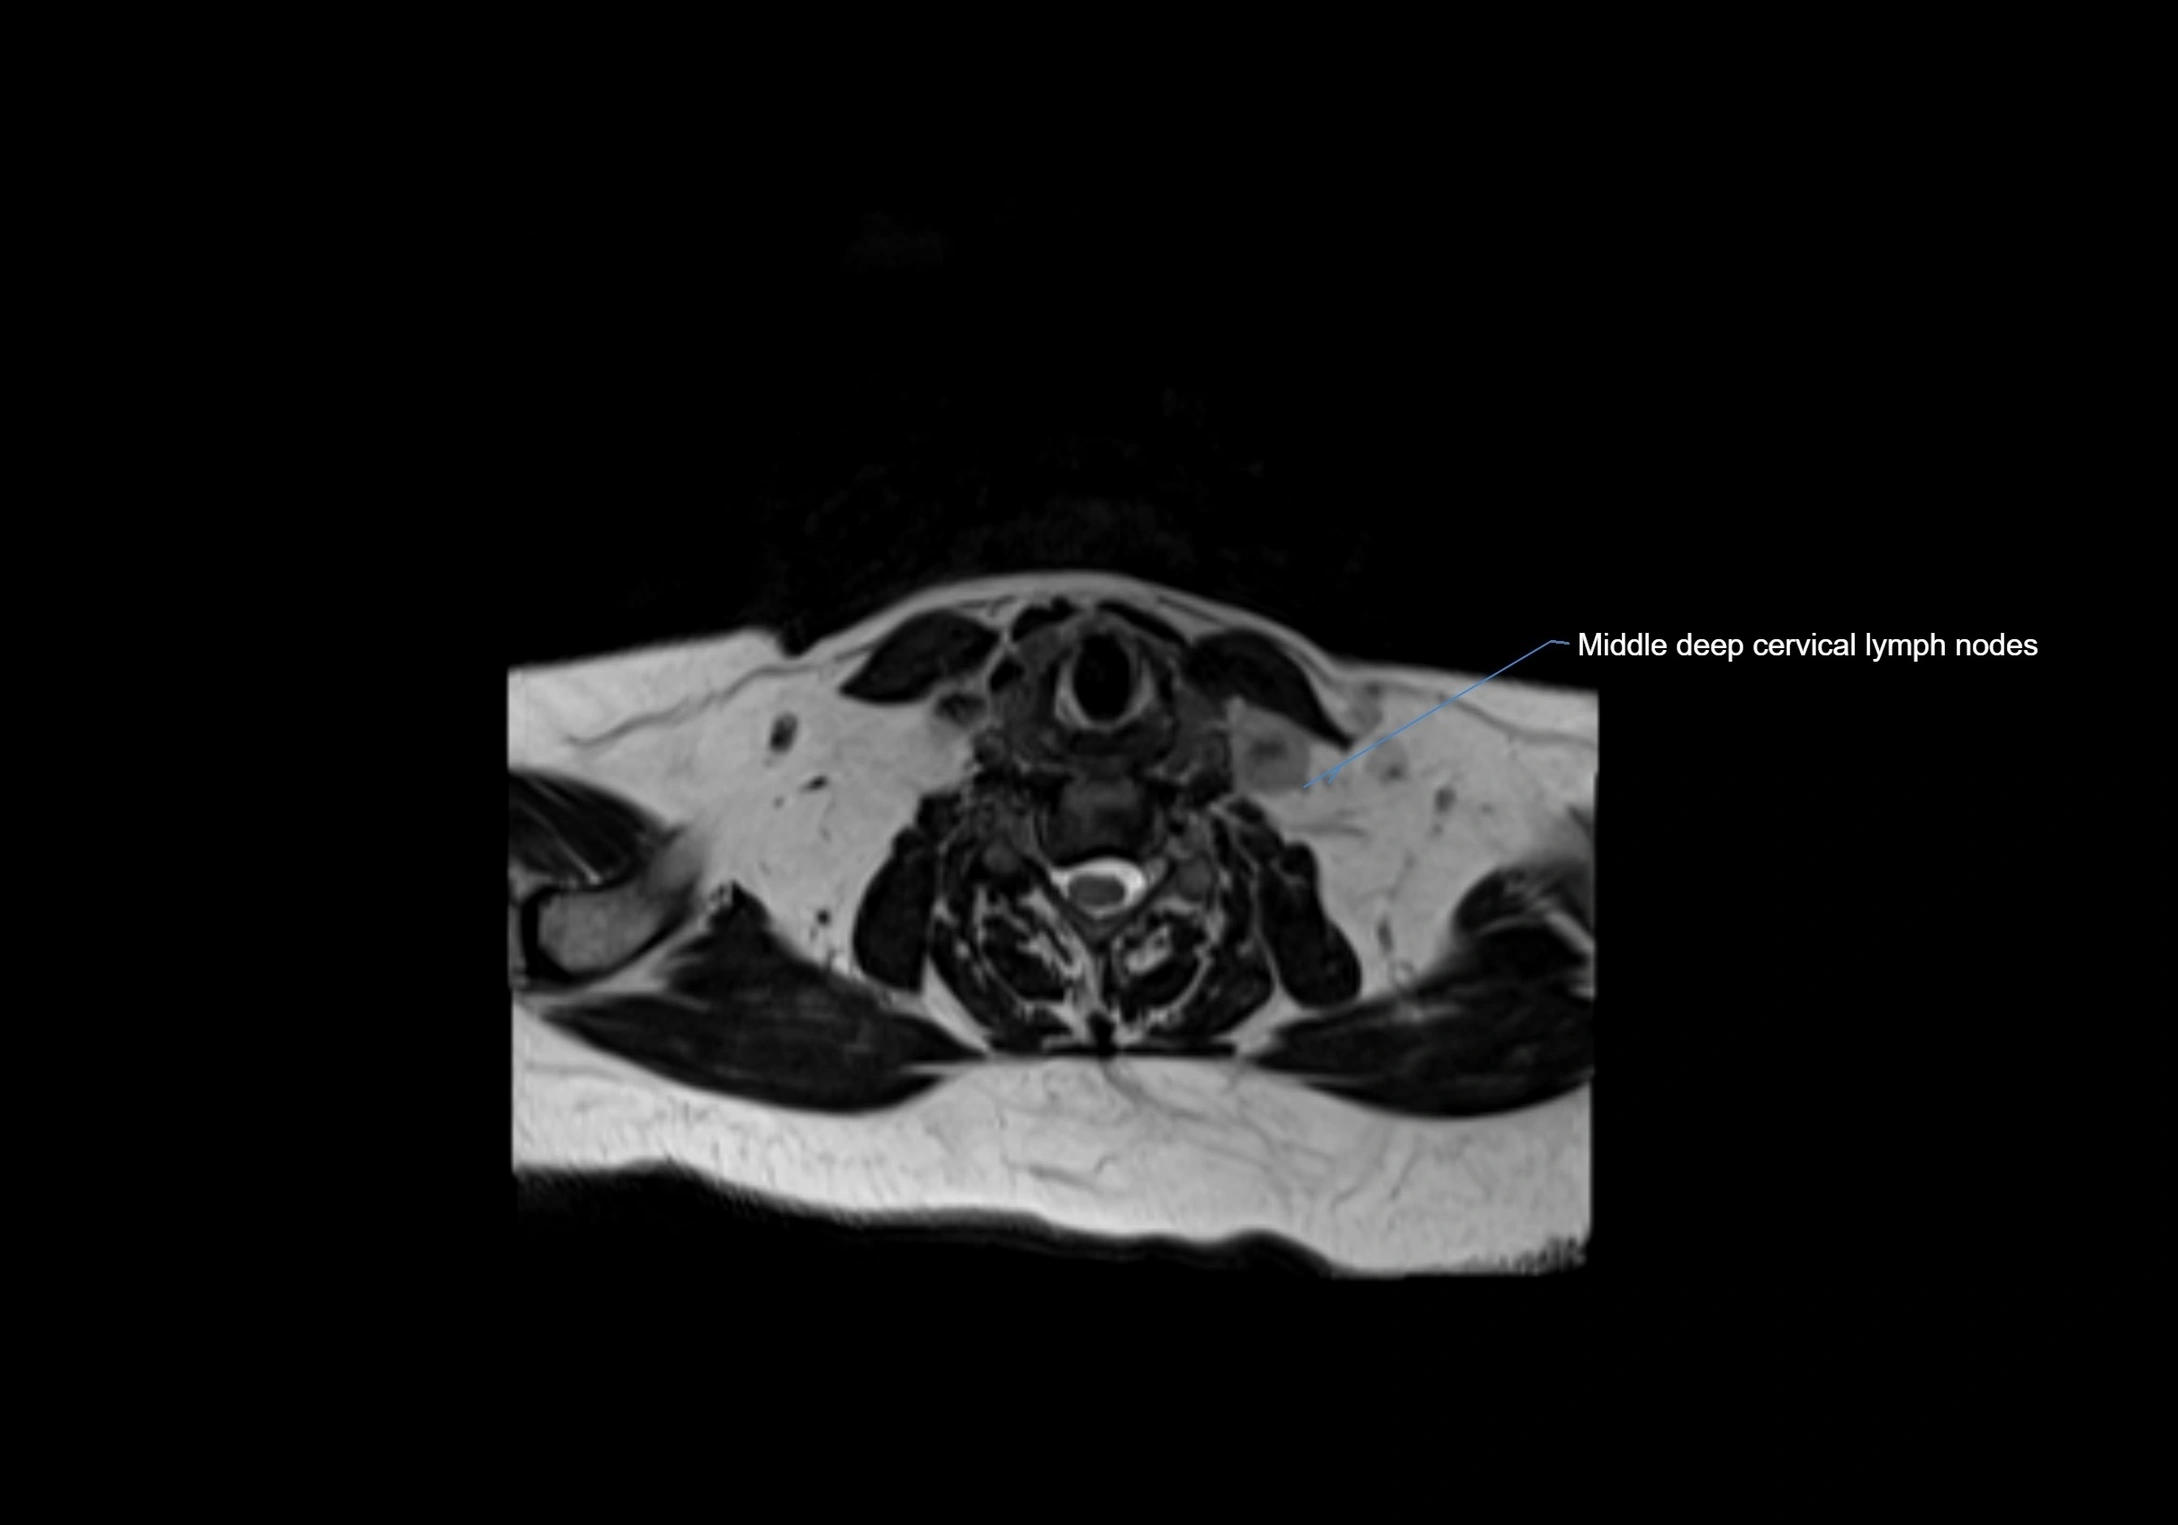

Accessory lymph nodes

Accessory lymph nodes are small, secondary lymph nodes located along the main facial and cervical lymphatic chains, often adjacent to primary lymph nodes, such as preauricular, submandibular, or occipital nodes. They are typically less than 5 mm in diameter, embedded within subcutaneous fat or connective tissue, and may be variable in number and location. These nodes provide additional filtration and immune surveillance for lymph collected from the face, scalp, and neck regions. Accessory lymph nodes are usually non-palpable in healthy individuals but may enlarge in response to infection, inflammation, or metastasis, making them clinically significant.

MRI Appearance

T2-weighted images:

• Nodes show intermediate signal, with surrounding fat bright

• Useful for detecting edema, inflammation, or infiltration

• Fatty hilum may appear slightly hyperintense relative to cortex

STIR (Short Tau Inversion Recovery):

• Fat suppression enhances visualization of edematous or pathological nodes

• Normal nodes appear low to intermediate signal, while inflamed or metastatic nodes appear hyperintense

• Useful for detecting subtle lymphadenopathy or early pathology

MRI images

image